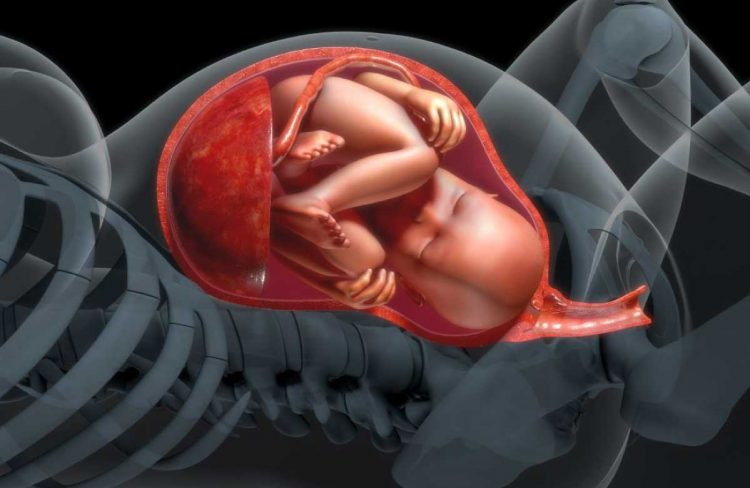

Polyhydramnios is a disorder that affects a pregnant woman’s uterus. In this disease, the uterus fills with too much amniotic fluid (the liquid that surrounds the baby in the womb). When this happens, the uterus expands beyond its typical size.

The symptoms of polyhydramnios are caused by pressure within the uterus and on adjacent organs.

Your uterus will be measured by a doctor to see if it is too large. That usually signifies you’re measuring two weeks or more ahead of your due date.